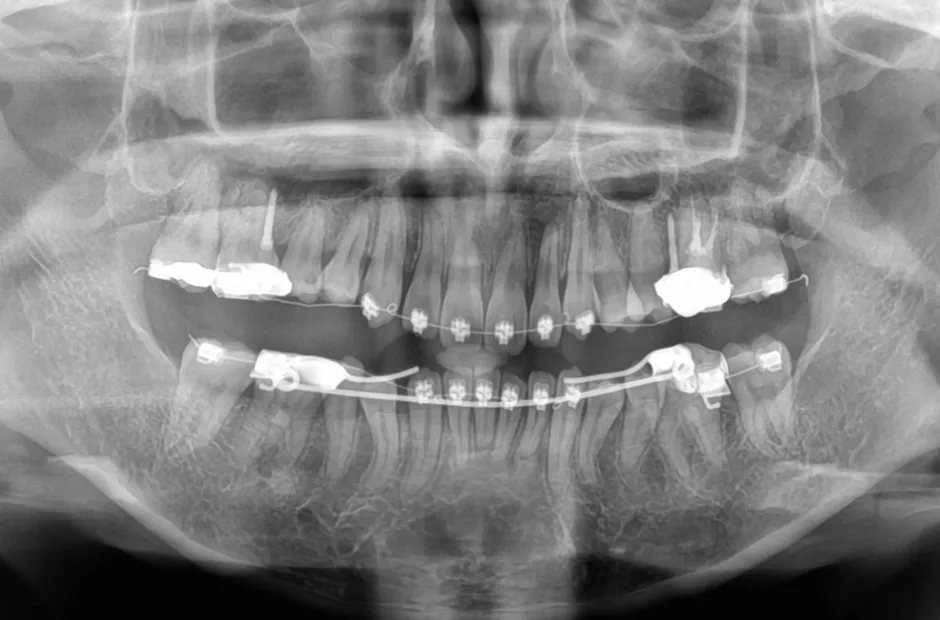

| 診断名・主訴 | 下顎前突、叢生 |

|---|---|

| 年齢・性別 | 23歳・女性 |

| 治療期間・回数 | 3年 |

| 治療に用いた主な装置 | 上顎5,5 下顎4,4 |

| 抜歯部位 | 舌側矯正 |

| 治療費 | 100万円(税抜) |

| リスク・副作用 | 装置による違和感・疼痛・歯肉退縮・歯根吸収・虫歯のリスクなど |

治療中